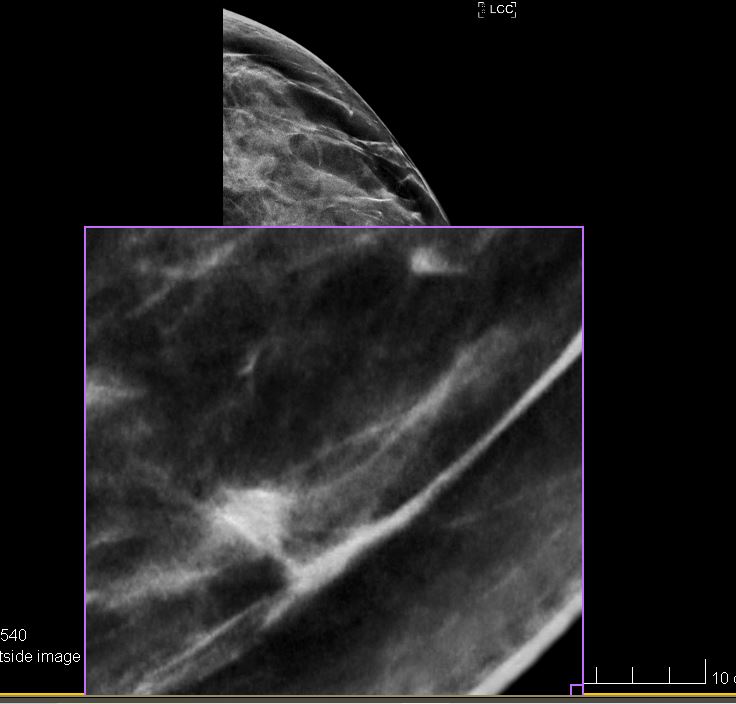

Здравствуйте. Мне 40 лет, мама и тётя болели раком груди. Надавно сделала первую мамограмму + 3D томосинтез, сегодня получила негативный результат (М1, все хорошо, никаких подозрительных изменений).

Но я вижу, что в левой груди есть какое-то образование. Переживаю. Как вы думаете, что это может быть? Стоит ли переделать в другом месте, или все выглядит нормально?

Все фото одной груди (левой).

С увеличением выглядит так: